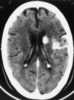

Subacute cortical infarction